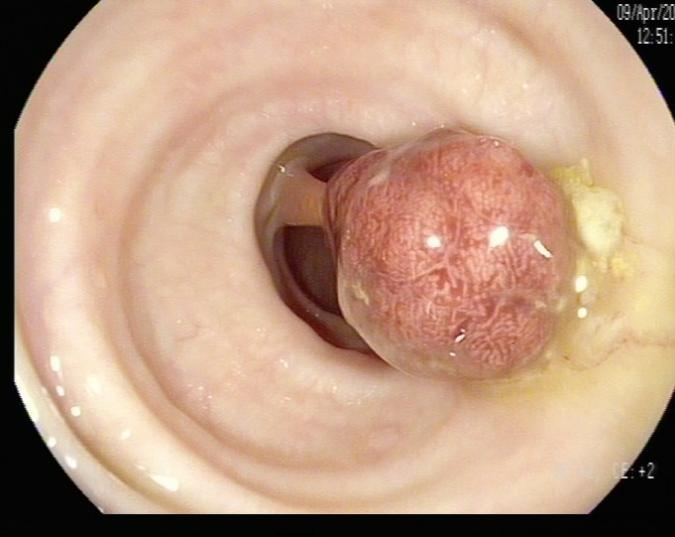

(1)赖女士(62岁,横结肠息肉,图1)

肠镜一照,息肉现形!形态各异的大肠息肉,离癌有多远?(图1)

图1

病理诊断:管状腺瘤,伴低级别上皮内瘤变。

解读:管状腺瘤是最常见的腺瘤性息肉。低级别上皮内瘤变意味着腺体结构和细胞出现了轻度到中度的异常改变,是明确的癌前状态。此阶段积极切除并定期复查,可有效阻断癌变进程。距离癌:一步之遥,癌前病变中期。